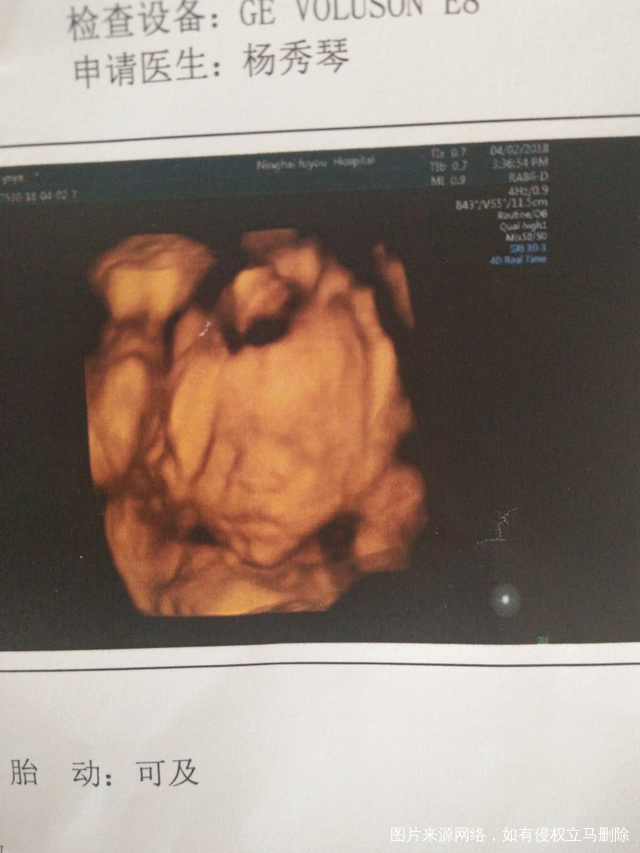

好奇的心你是女儿还是儿子呀